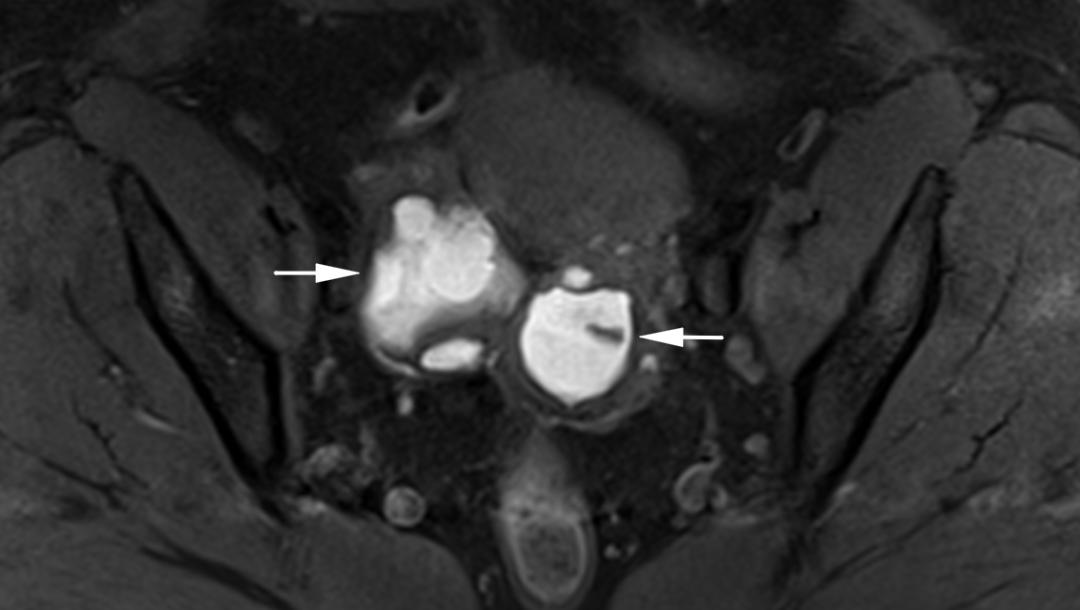

子宫内膜异位至右侧卵巢,T2WI 轴位发现右侧附件区「葫芦形」高信号,但是更应该注意的是病灶右侧带状低信号,提示与周围结构的黏连。